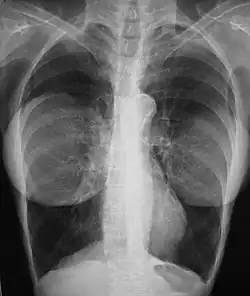

Mammography

The presence of radiologically opaque breast implants (either saline or silicone) might interfere with the radiographic sensitivity of the mammograph, that is, the image might not show any tumor(s) present. In this case, an Eklund view mammogram is required to ascertain either the presence or the absence of a cancerous tumor, wherein the breast implant is manually displaced against the chest wall and the breast is pulled forward, so that the mammograph can visualize a greater volume of the internal tissues; nonetheless, approximately one-third of the breast tissue remains inadequately visualized, resulting in an increased incidence of mammograms with false-negative results.[117][118]

The breast cancer studies Cancer in the Augmented Breast: Diagnosis and Prognosis (1993) and Breast Cancer after Augmentation Mammoplasty (2001) of women with breast implant prostheses reported no significant differences in disease-stage at the time of the diagnosis of cancer; prognoses are similar in both groups of women, with augmented patients at a lower risk for subsequent cancer recurrence or death.[119][120] Conversely, the use of implants for breast reconstruction after breast cancer mastectomy appears to have no negative effect upon the incidence of cancer-related death.[121] That patients with breast implants are more often diagnosed with palpable—but not larger—tumors indicates that equal-sized tumors might be more readily palpated in augmented patients, which might compensate for the impaired mammogram images.[122] The ready palpability of the breast-cancer tumor(s) is consequent to breast tissue thinning by compression, innately in smaller breasts a priori (because they have lesser tissue volumes), and that the implant serves as a radio-opaque base against which a cancerous tumor can be differentiated.[123]

The breast implant has no clinical bearing upon lumpectomy breast-conservation surgery for women who developed breast cancer after the implantation procedure, nor does the breast implant interfere with external beam radiation treatments (XRT); moreover, the post-treatment incidence of breast-tissue fibrosis is common, and thus a consequent increased rate of capsular contracture.[124] There is tentative evidence that women who have had breast augmentation, have worse breast cancer prognosis.[125] The use of implants for breast reconstruction after breast cancer mastectomy appears to have no negative effect upon cancer-related death.[121][126]

There have been multiple reported cases of other adverse effects of mammography of women with breast implants; ruptures resulting from pressure exerted on the breast implant make up a majority of these cases.[127] Compression may also lead to pain or exacerbate already existing pain in the breasts.[127]